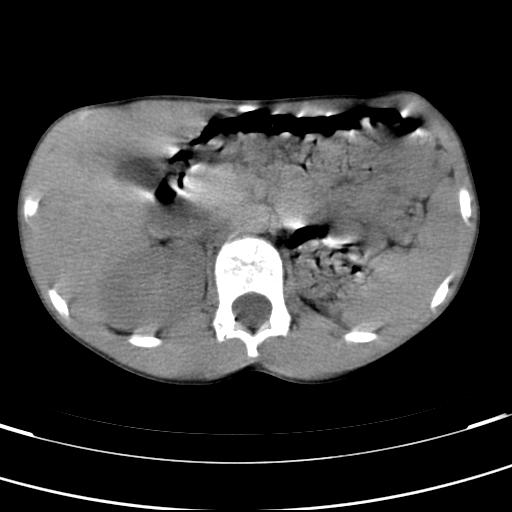

标题: PED3157:左肾缺如,请教脾脏的改变?、、

男孩,9岁。胃部不适。

脾脏位于左侧,但数个脾脏呈分离状态,左肾缺如,右肾代偿肥大。考虑多脾综合征。